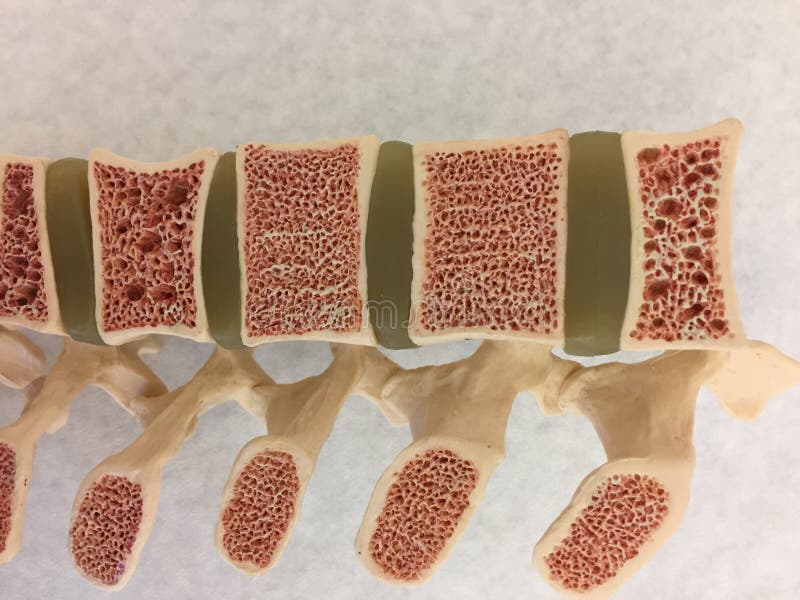

Изучение костного мозга: анатомия и функции